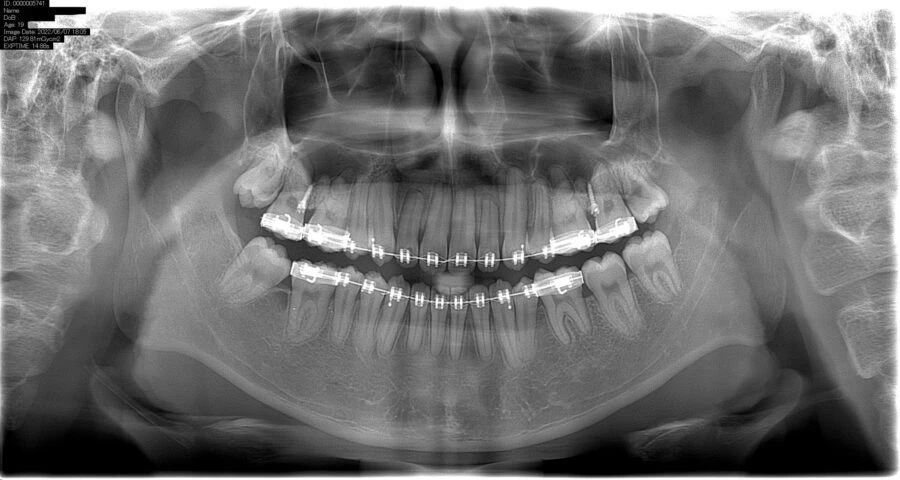

Phim X-quang toàn cảnh (còn được gọi là pantomography) là một kỹ thuật tạo một hình ảnh một lớp của các cấu trúc mặt bao gồm xương hàm trên và cung răng hàm dưới và những cấu trúc nâng đỡ chúng.

Đây là một đường cong biến thể của hình ảnh một lớp truyền thống và cũng dựa trên nguyên tắc chuyển động thuận nghịch của một nguồn tia X và một receptor nhận ảnh xung quanh một điểm trung tâm hoặc mặt phẳng, được gọi là lớp nhận ảnh, trong đó đặt vật thể quan tâm. Vật thể đặt trước hoặc sau lớp nhận ảnh này không được chụp rõ vì sự chuyển động của nó tương đối với tâm xoay của receptor và nguồn tia X.

Phim x-quang toàn cảnh hầu hết là hữu ích trên lâm sàng để chẩn đoán những vấn đề cần sự quan sát tổng thể xương hàm. Những dẫn chứng thông thường bao gồm chấn thương, vị trí răng cối lớn thứ ba, bệnh lý xương và răng lan rộng, nghi ngờ những tổn thương lớn, sự phát triển của răng (đặc biệt là ở bộ răng hỗn hợp), những răng còn lại hoặc chóp chân răng (ở những bệnh nhân bất răng), đau khớp thái dương hàm và những bất thường do phát triển. Những chức năng này không đòi hỏi độ những hình ảnh có phân giải cao và sắc nét trong miệng.

Phim x-quang toàn cảnh thường được sử dụng để đánh giá hình ảnh ban đầu nhằm cung cấp thông tin cần thiết hoặc hỗ trợ để xác định nhu cầu chụp những hình ảnh khác. Phim toàn cảnh cũng hữu ích đối với những bệnh nhân không thực hiện chụp những phim trong miệng tốt được. Tuy nhiên, khi một loạt các phim chụp trong miệng có thể thực hiện được cho một bệnh nhân cần chăm sóc sức khỏe răng miệng tổng quát thì nhìn chung nếu chụp đồng thời thêm một phim toàn cảnh nữa sẽ có ít hoặc không có thông tin thêm nào từ nó.

Nhược điểm chính của phim x-quang toàn cảnh là hình ảnh không hiển thị những chi thiết giải phẫu nhỏ như ở him quanh chóp. Vì vậy, nó không hữu ích bằng phim x-quang quanh chóp khi muốn phát hiện những tổn thương sâu răng nhỏ, cấu trúc nhỏ của bờ mô nha chu, hoặc bệnh lý quanh chóp. Những bề mặt tiếp xúc của các răng cối nhỏ cũng thường bị chồng lên nhau. Do đó, việc thực hiện phim x-quang toàn cảnh ở một bệnh nhân trưởng thành thường không loại trừ nhu cầu chụp phim trong miệng để chẩn đoán những bệnh lý về răng thường gặp.

Những vấn đề khác liên quan đến phim x-quang toàn cảnh bao gồm sự phóng đại không bằng nhau và biến dạng hình học dọc theo hình ảnh. Đôi khi sự hiện diện của những cấu trúc chồng lên nhau có thể che lấp đi những tổn thương có nguồn gốc do răng, đặc biệt là vùng răng cửa. Hơn nữa, những điểm lâm sàng quan trọng có thể nằm ngoài mặt phẳng lấy nét (lớp ảnh) và có thể bị biến dạng hoặc hoàn toàn không hiển thị.